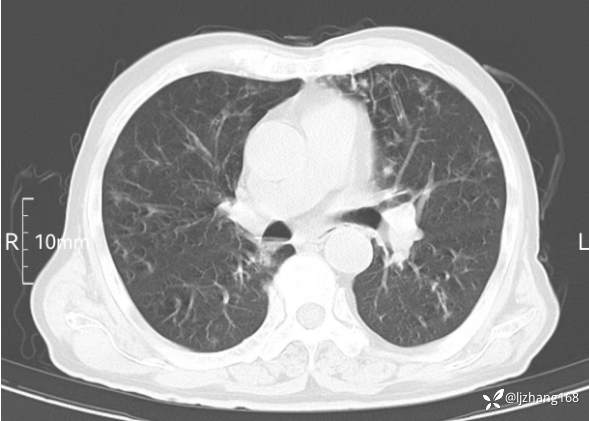

老年男患,咳嗽,气短,双肺多发间质性病变,何种感染?(有结果)

辅助检查:胸部CT:双肺肺气肿,间质性病变,血气分析:PH 7.413, PCO2 29.2mmHg, PO2,81.8mmHg,乳酸 3.3mmol/1,剩余碱-4.0mmol/1,HC03 18.8mmol/1。全血超敏C反应蛋白:超敏C反应蛋白 135.60 mg/L、 白细胞 14x19^9/L,中性粒细胞11.6x10^9/L。